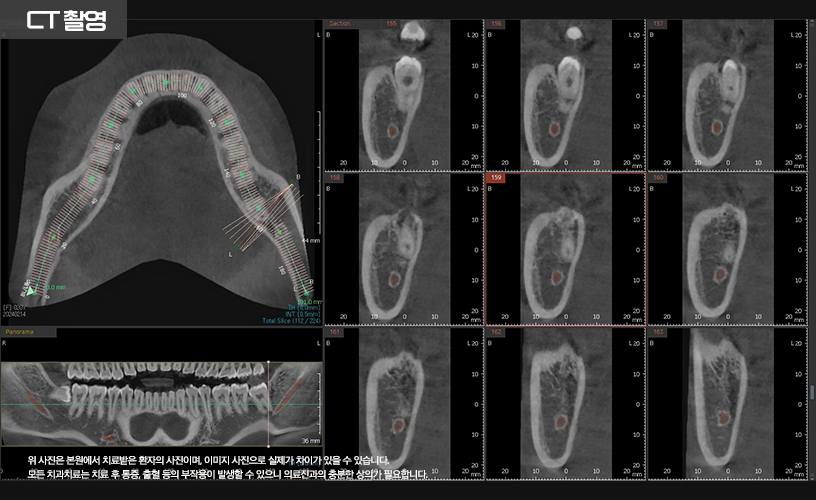

발치 전 3D CT 촬영을 통해

사랑니와 하치조 신경의 위치를

정확히 파악하는 것이 필수적입니다.

CT 촬영을 통해 신경관과 사랑니의 위치를

파악한 다음 발치가 이루어졌습니다.